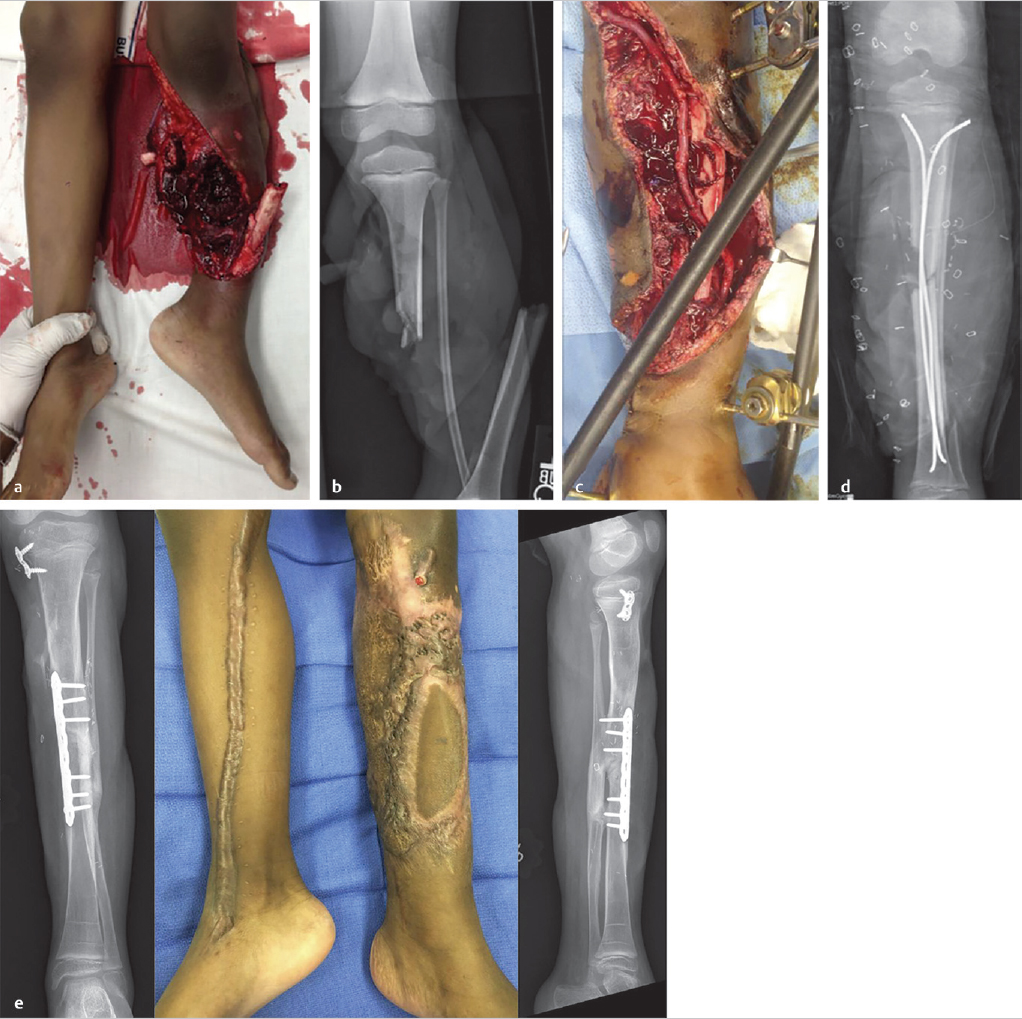

▶ Fig. 4.1 demonstrates a representative case of an 8-year-old child with a Gustilo 3C injury to the lower extremity where these principles were applied. This orthoplastic approach led to successful limb salvage and a good outcome.